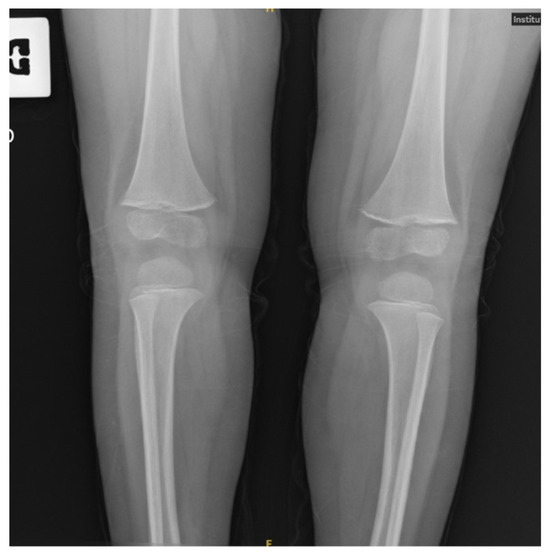

Background and Clinical Significance: Scurvy, caused by chronic vitamin C deficiency, is re-emerging in Western countries, particularly among pediatric patients with highly selective diets. While its musculoskeletal and mucocutaneous manifestations are well-known, its association with pulmonary arterial hypertension (PAH) is rare and poorly understood. Ascorbic acid and iron are essential cofactors for prolyl hydroxylases (PHD), which regulate Hypoxia-Inducible Factors. Their combined deficiency may trigger a “pseudohypoxic” state, leading to pulmonary vascular remodeling and vasoconstriction. Case Presentation: A 30-month-old female presented with a one-month history of limping, lower limb pain, and gingival hypertrophy. Dietary history revealed an almost exclusive cow’s milk-based intake. Physical examination showed diffuse petechiae, pallor, and right knee edema. Laboratory findings confirmed scurvy (undetectable vitamin C), severe iron-deficiency anemia (Hb: 72 g/L; ferritin: 22 mcg/L; RDW: 30%), folate deficiency, and hyperhomocysteinemia. Notably, elevated copper and vitamin B12 levels suggested a state of metabolic dysregulation. Echocardiography revealed moderate PAH phenotype (estimated sPAP: 47–50 mmHg) and a hyperdynamic contractility. A “perfect storm” mechanism was hypothesized, involving iron–ascorbate-dependent PHD impairment, high-output state, and oxidative-stress-induced hepcidin dysregulation (suggested by elevated copper). Following intravenous vitamin C and multivitamin supplementation, pulmonary pressures normalized within one week. Conclusions: PAH phenotype in scurvy represents a reversible metabolic disruption of pulmonary vascular tone rather than a structural disease. This case underscores the synergistic role of vitamin C, iron, and folate in vascular homeostasis. Clinicians should maintain high suspicion for scurvy in children with selective diets and unexplained PAH, as nutritional restoration is curative. Full article